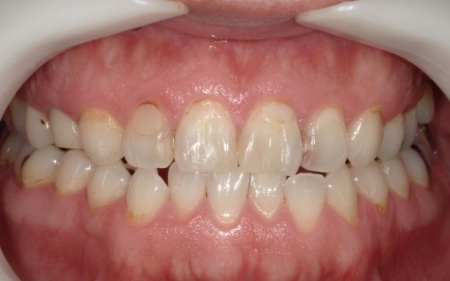

40代男性 長年放置していた虫歯や根尖性歯周炎などの口腔トラブルを全体的に治療した症例

「虫歯を長年放置してしまったので治療をしたい。また、見た目や噛み合わせの改善などを含めた、全体的な治療も行いたい」とご相談いただきました。

口腔内の健康状態を改善しつつ、歯磨きなどのケアをしやすくするために、以下の治療方法を提案して同意いただきました。

まず、虫歯部分を丁寧に取り除いてから歯の形を整え、CRを詰めてしっかりと研磨します。

最後に、古いアマルガムを除去した部分は保険診療の範囲で治療を行い、見た目や噛み合わせなどに問題がないことを確認して、治療を終了しています。